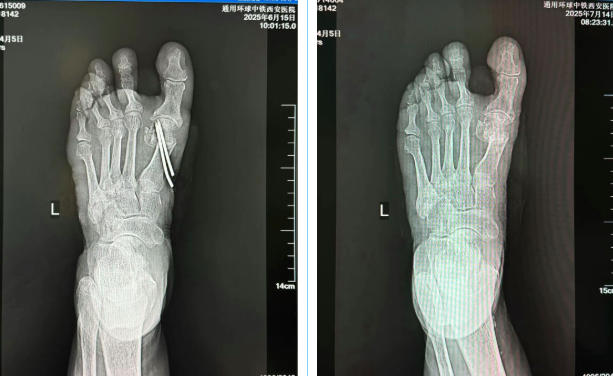

术前影像图

术后影像图

术前/术后